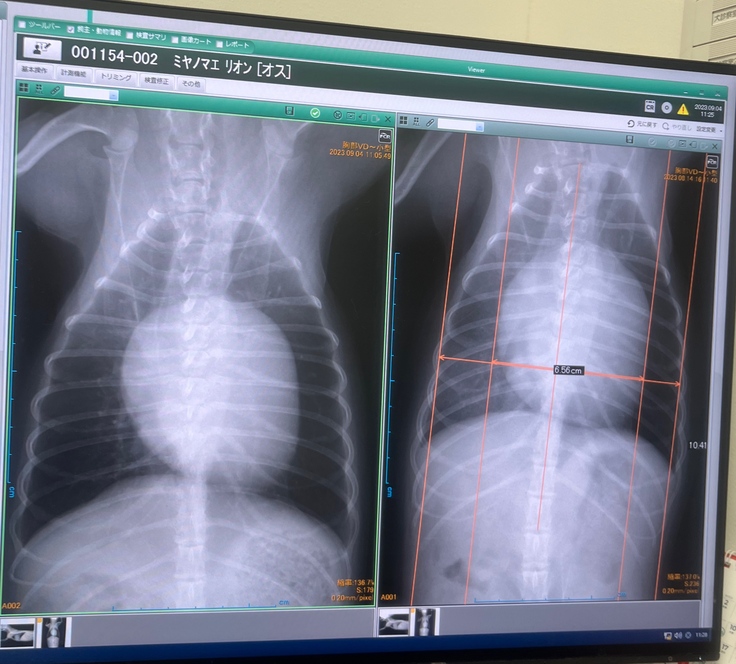

獣医師の説明によると、健康な子の心臓の大きさの3倍腫れ上がっています。と、、、

かかりつけ病院の診断書(病院名は隠してあります。先生の掲載許可済み)

手術を行う病院の診断書(病院名は隠してあります。先生の掲載許可済み)

12日間の投薬のおかげでほんの少しだけ小さくなったとの事です。

検査結果